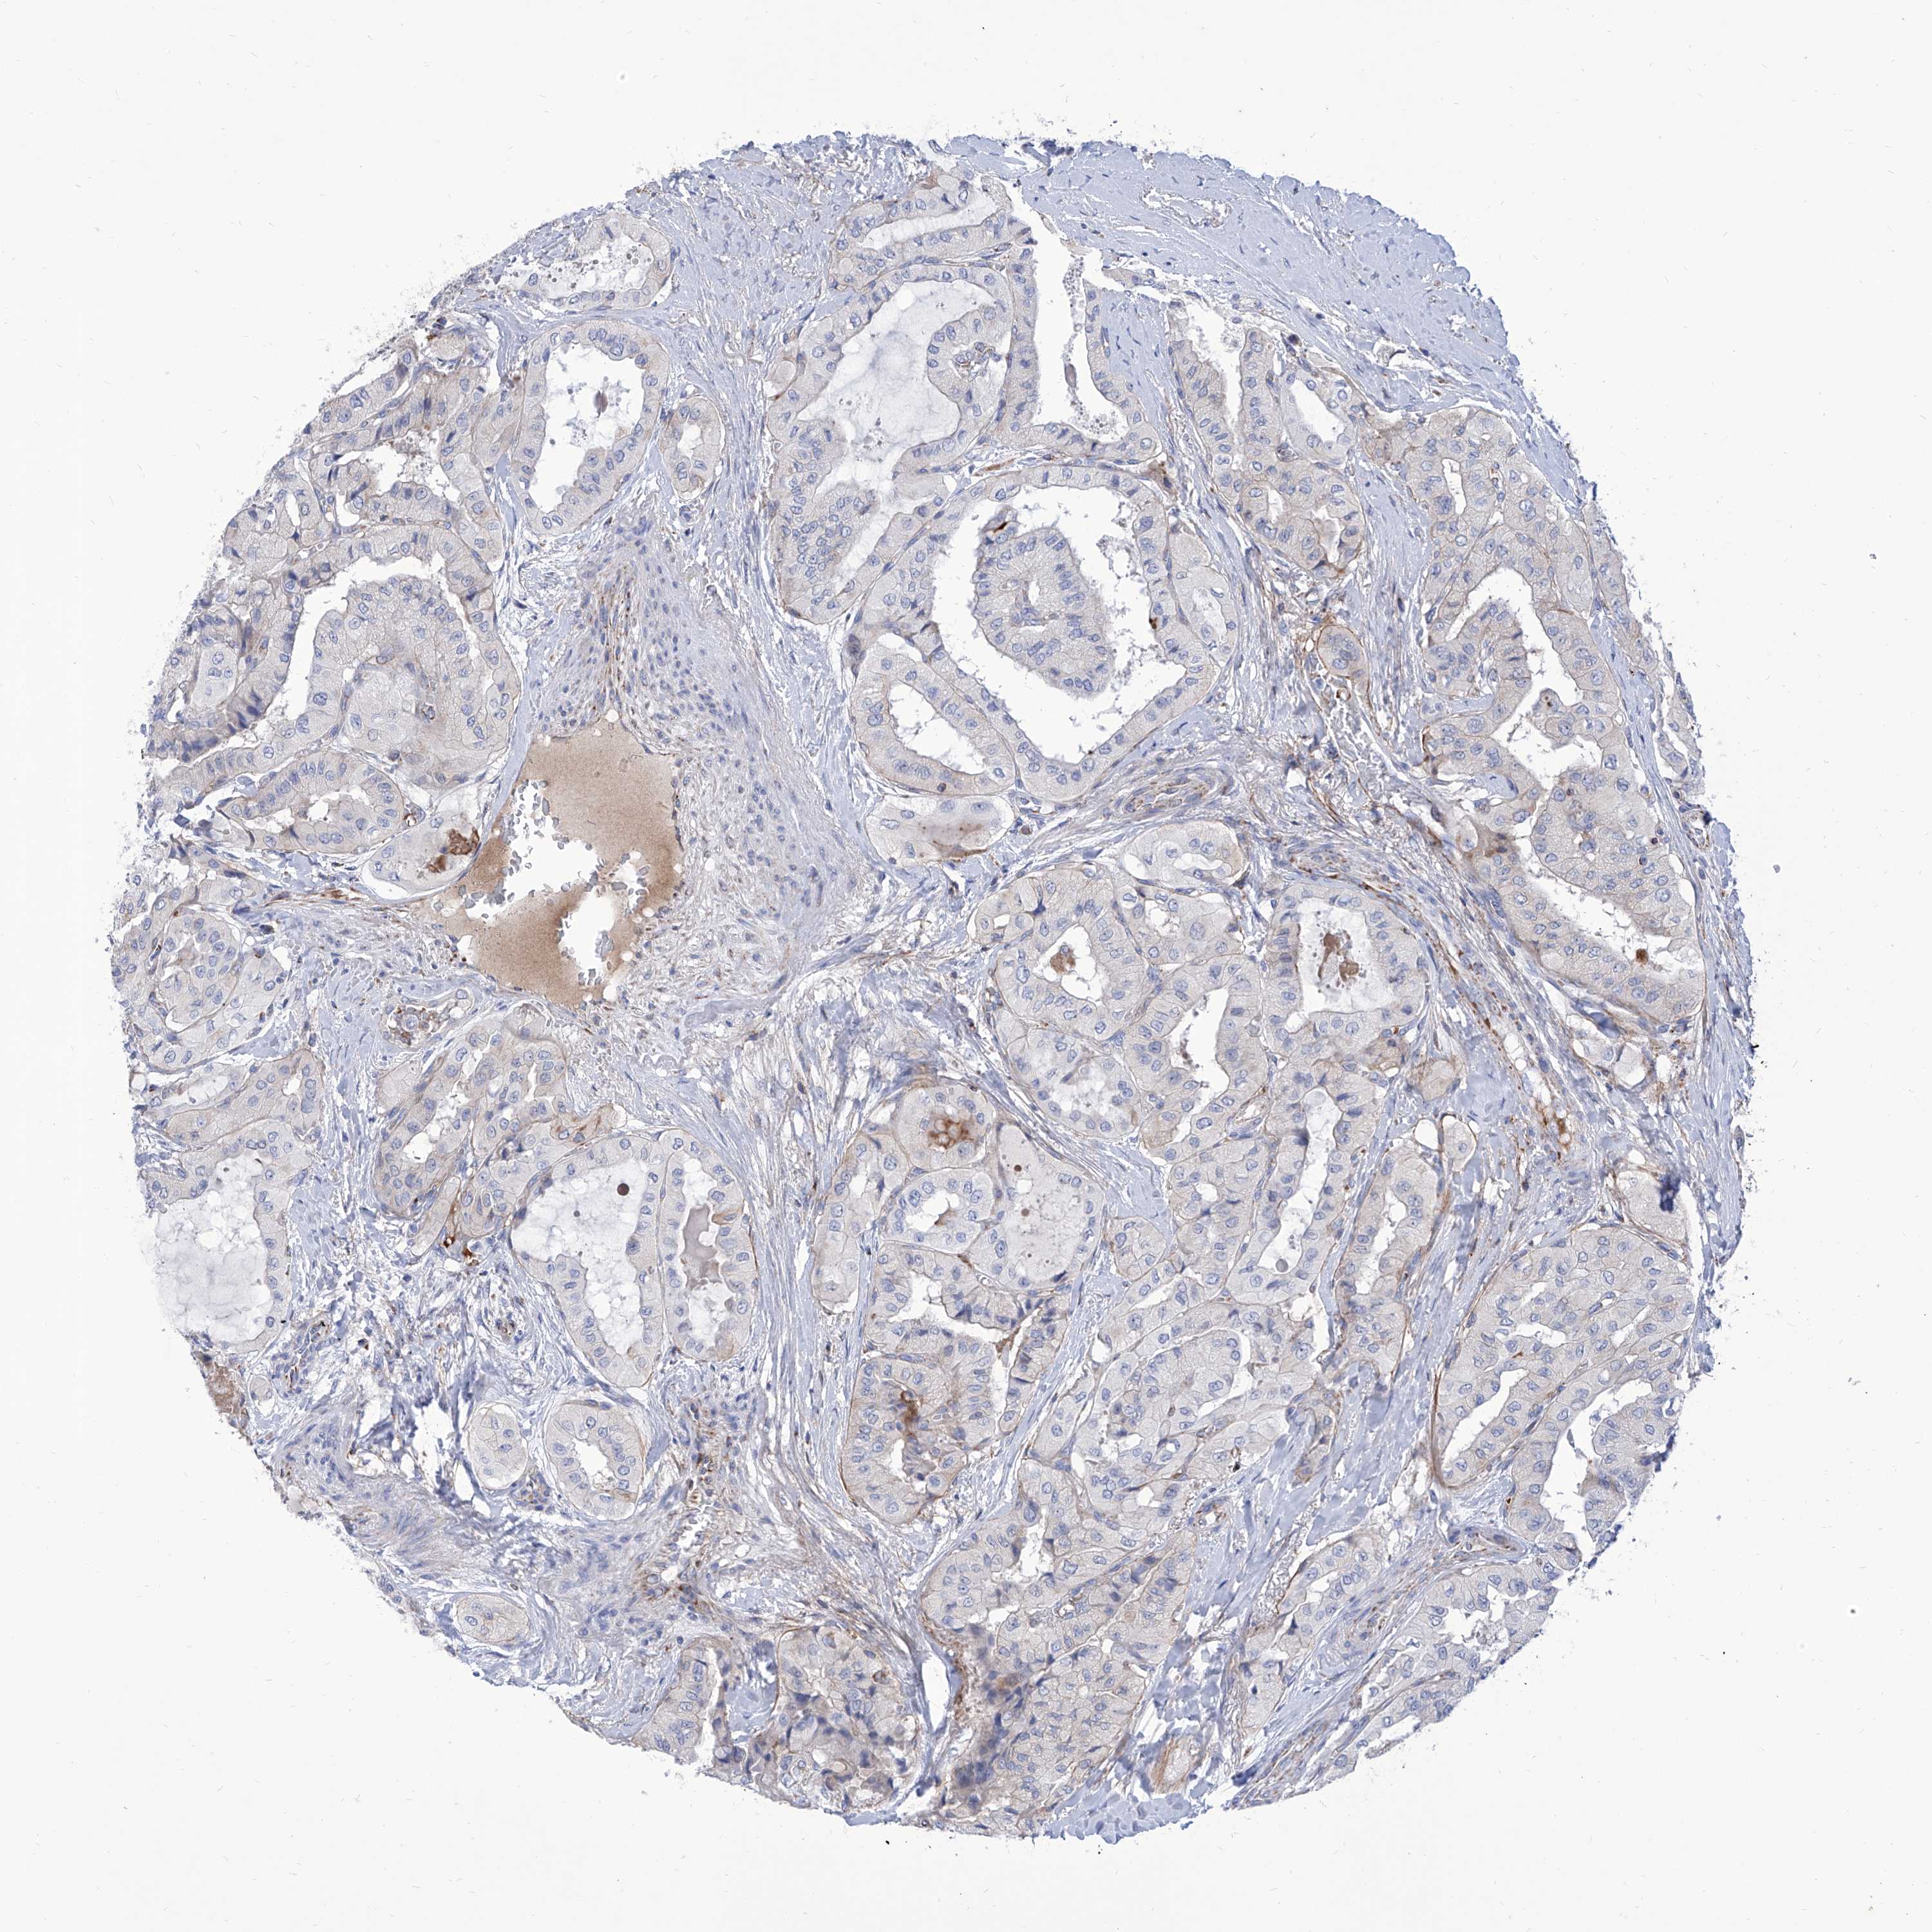

THYROID CANCER - Protein expressioni

A mouse-over function shows sample information and annotation data. Click on an image to view it in a full screen mode. Samples can be filtered based on level of antibody staining by selecting one or several of the following categories: high, medium, low and not detected. The assay and annotation is described here.

Note that samples used for immunohistochemistry by the Human Protein Atlas do not correspond to samples in the TCGA dataset.

Antibody stainingi

Antibody staining in the annotated cell types in the current human tissue is reported as not detected, low, medium, or high, based on conventional immunohistochemistry profiling in selected tissues. This score is based on the combination of the staining intensity and fraction of stained cells.

Each image is clickable and will lead to virtual microscopy that enables deeper exploration of all samples and also displays staining intensity scores, fraction scores and subcellular localization as well as patient and tissue information for each sample.

Antibody HPA030567

Antibody HPA030568

Staining

High

Medium

Low

Not detected

Intensity

Strong

Moderate

Weak

Negative

Quantity

>75%

75%-25%

<25%

None

Location

Nuclear

Cytoplasmic/membranous

Cytoplasmic/membranous,nuclear

Papillary adenocarcinoma, NOS

Follicular adenoma carcinoma, NOS